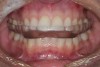

(1.) This SRS was fabricated for wear on the maxillary arch. The anterior contour allows the posterior teeth to separate in lateral and protrusive movements.

Figure 1

The primary splint used to treat an intracapsular problem is a superior repositioning splint (SRS), which is also known as a centric relation splint (Figure 1). These are full coverage permissive splints that can be made to cover the maxillary or the mandibular teeth. The goal of this appliance is to, in a reversable manner, meet Dawson's five requirements of occlusal stability:

Fabricating an SRS

An SRS must be fabricated utilizing facebow-mounted high-quality impressions or digital scans. For the splint to fit the occlusion correctly, the 3D orientation of the maxilla and the condylar axis of rotation must be recorded (Figure 2). The lower model should be mounted as close to centric relation as possible. To provide separation of the posterior teeth in excursive movements, an SRS should be as thin as possible and created with anterior contour. It should also be smooth, fit passively, and not rock on the dentition.9